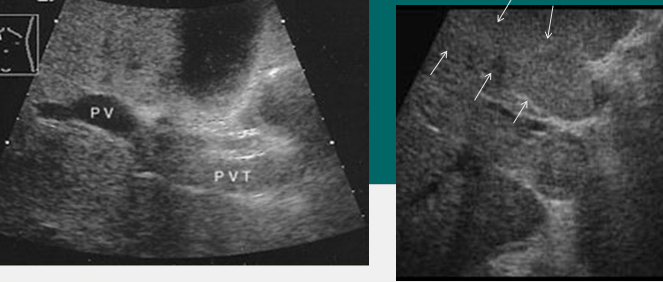

portal vein thrombosis (PVT)

portal vein stenosis (PVS)